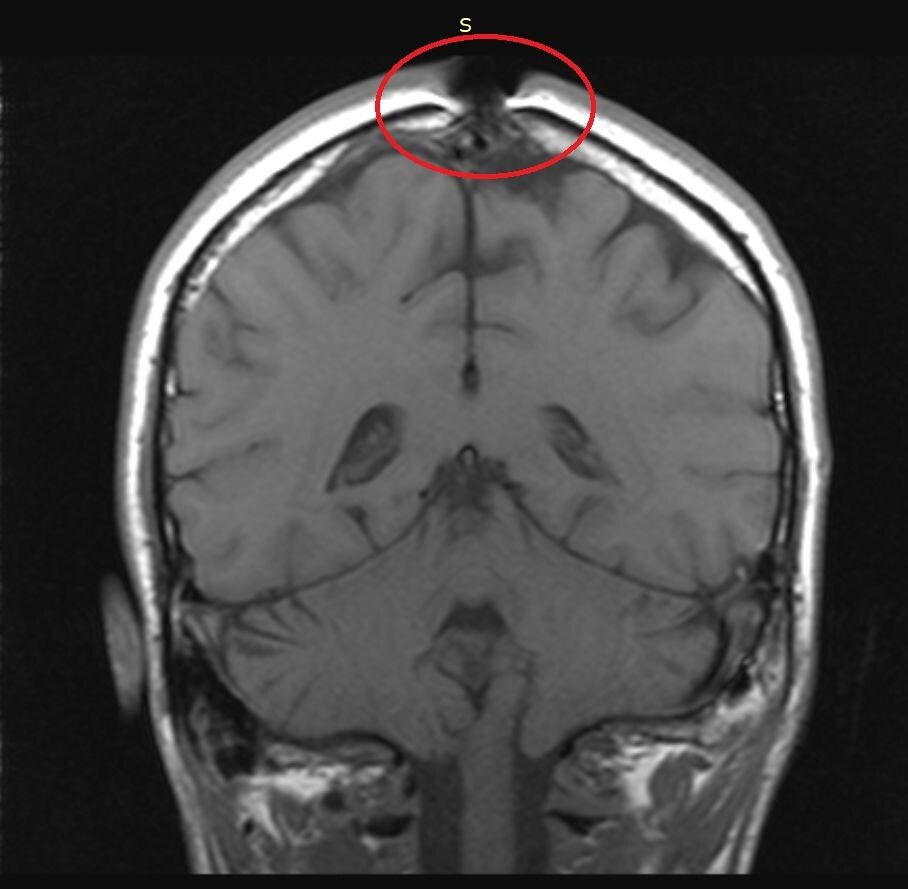

МРТ головы в прямой проекции.